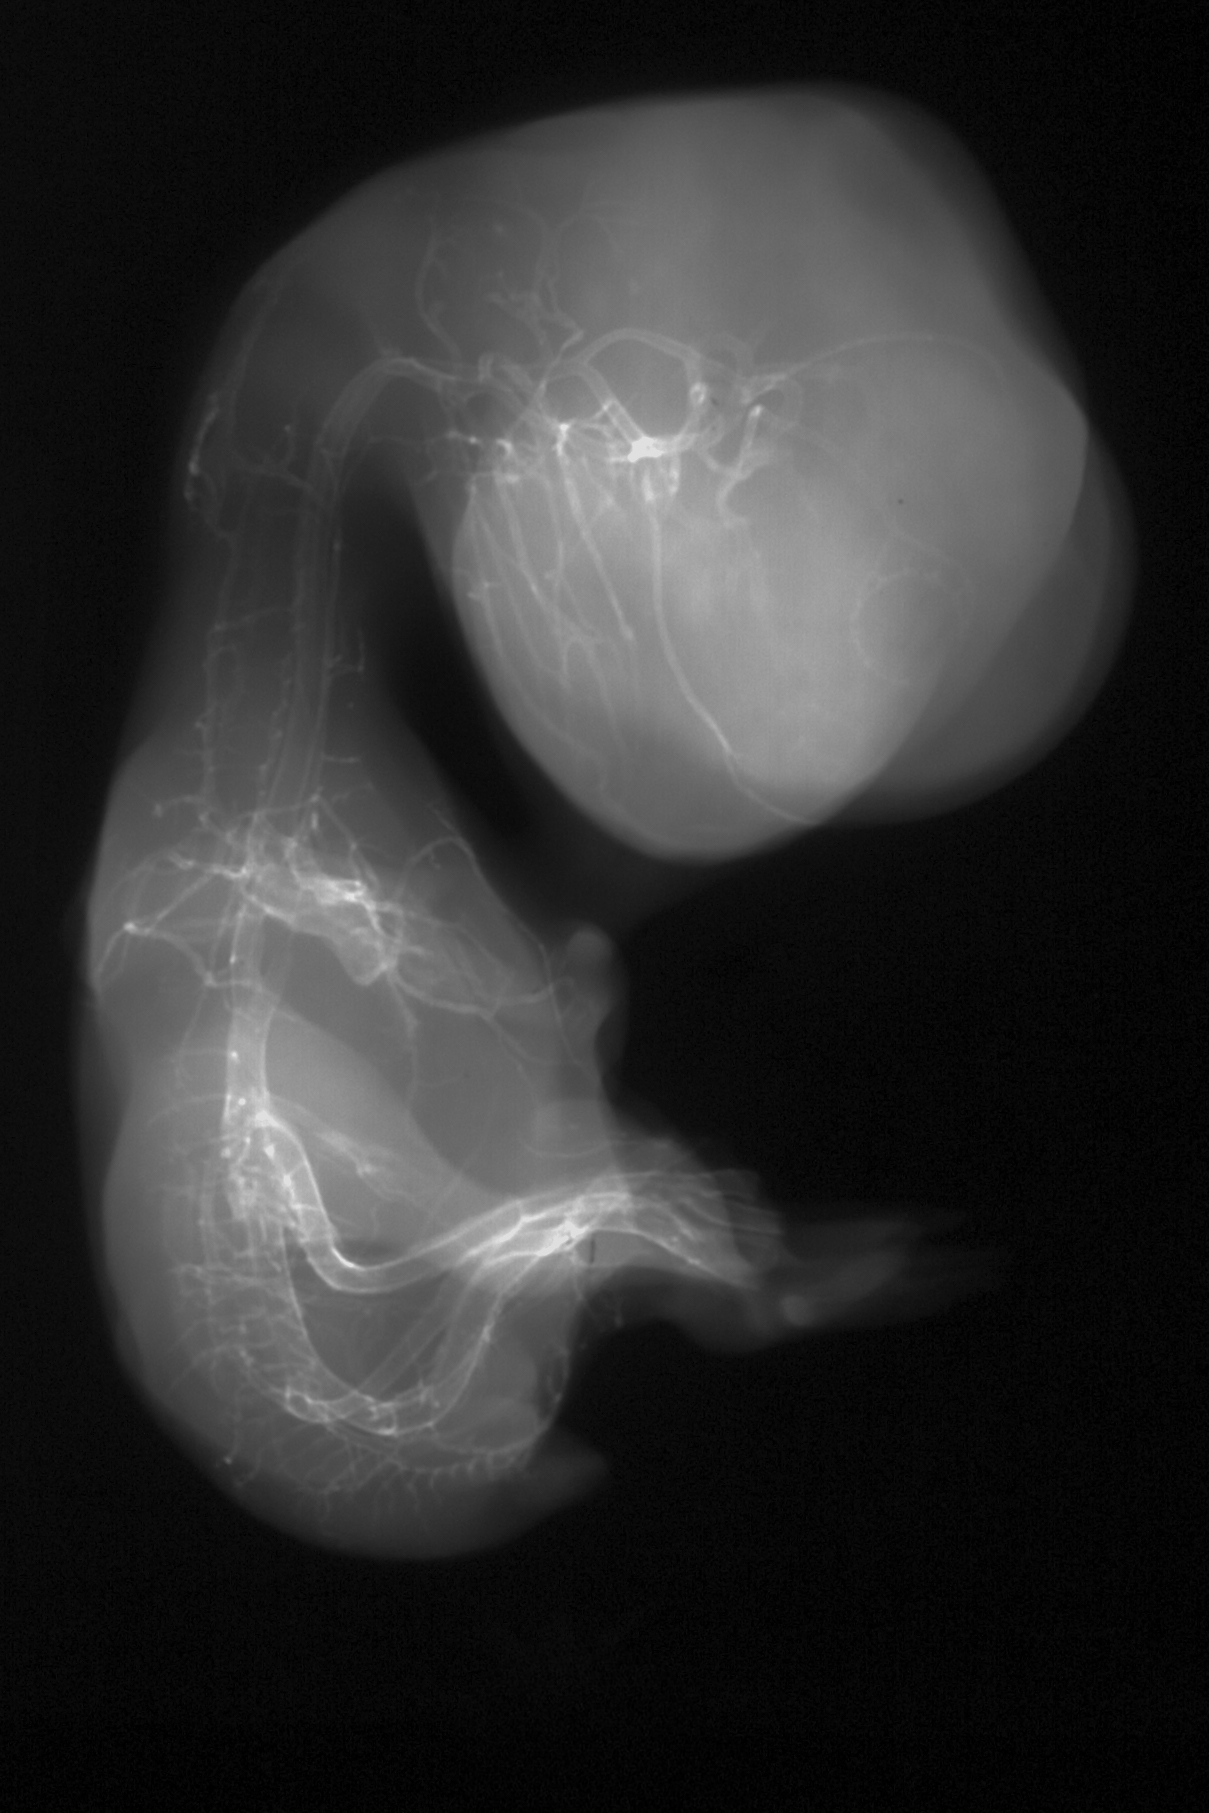

Chick Embryo Microangiography

Hamburger-Hamilton (HH) Stage 35 (approx. 8.5 - 9 days)

Stereo X-Ray Micrographs